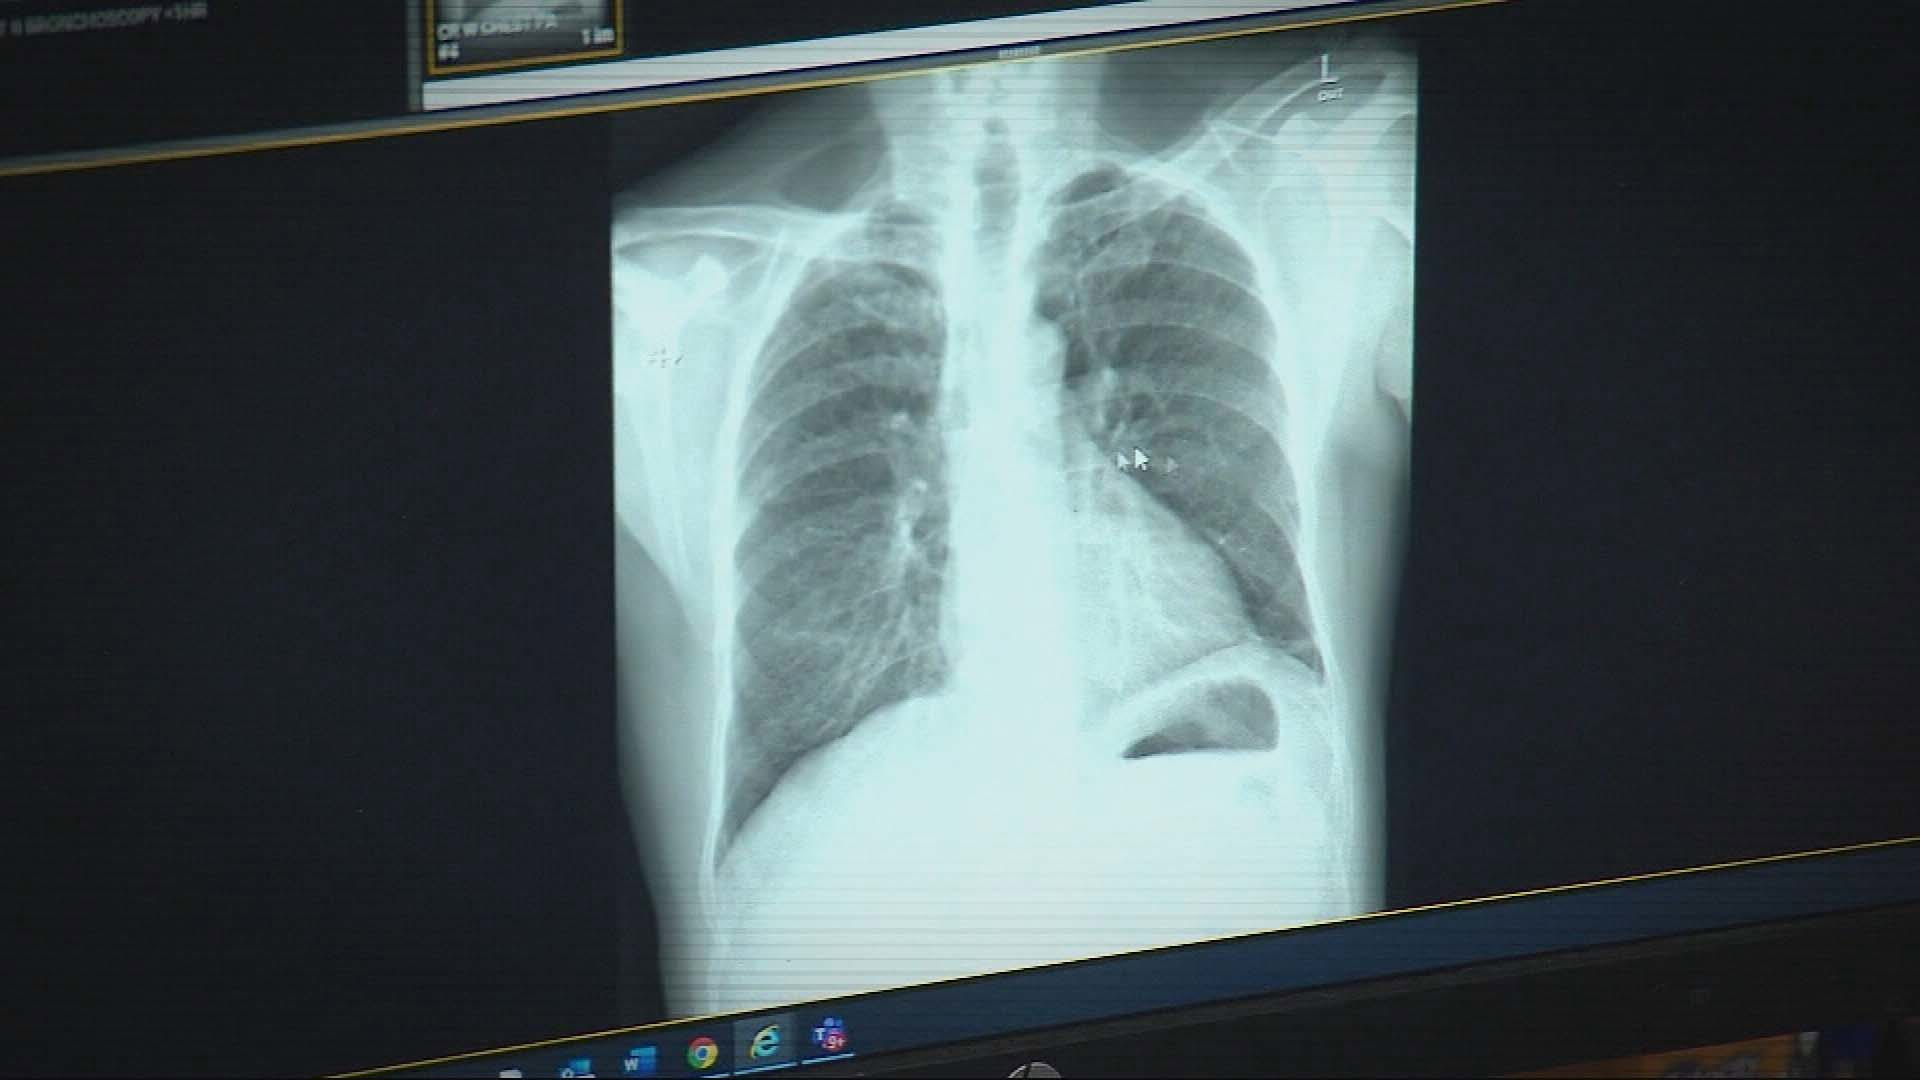

Silicosis is an incurable disease caused by inhaling small particles of silica dust and is typically associated with the synthetic stone benchtop industry.